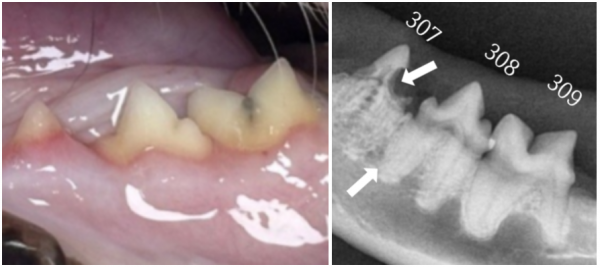

→ 치과 방사선에서 뚜렷하게

보이는 307번의 치아흡수성병변

치과 방사선 촬영에서

육안으로 확인되었던 치아 이외에도

다수의 치아가 흡수병변이 있는 것으로 확인되었습니다.

고양이 치아흡수성병변은

육안으로 확인이 어려운 경우가 많아

치과 방사선 촬영이 필수적입니다.

치아 내부의 흡수 정도와 남아 있는 치근 상태를 정밀하게 평가해야 합니다.